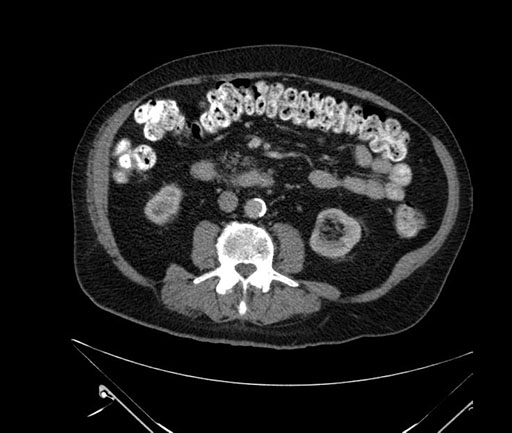

Whipple (pancreaticoduodenectomy) [case 7]

Imaging Analysis

Look through the patient's CT scan to identify any areas of concern for the necessary procedure.

Axial - 3 months prior